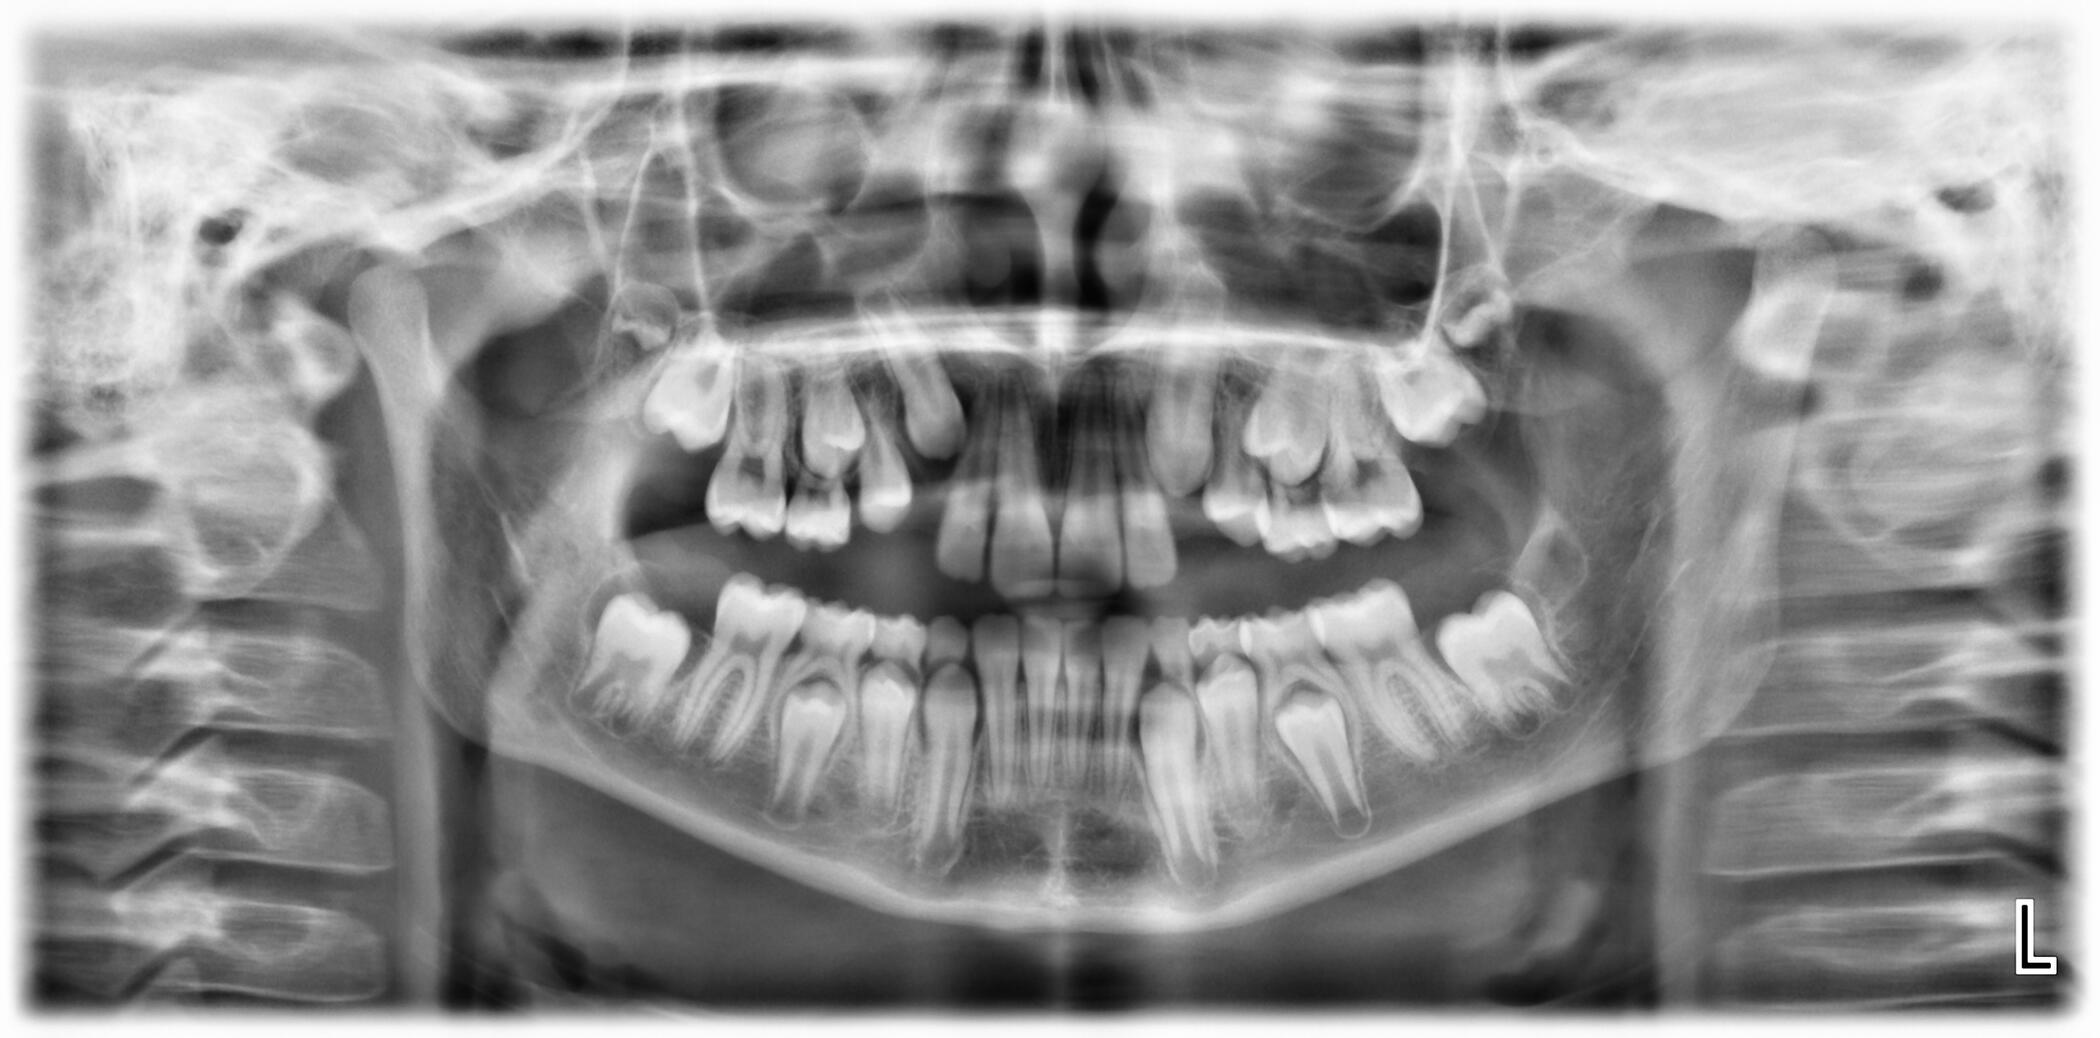

Ортопантомография / Панорамна снимка

Planmeca ProMax 2D

Ортопантомограф, който се характеризира с:

- около 80% по-малко облъчване спрямо конвенционалните апарати.- намалено време за експонация при запазване на висока диагностична стойност на графиите.- възможност за изследване на пациенти в инвалидни колички.- телерентгенографии с отличен контраст и изобразяване на меките тъкани.